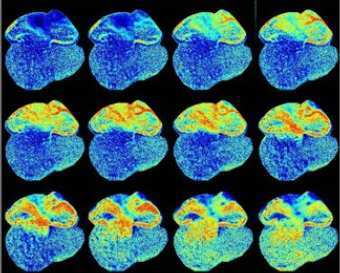

Флуоресцентные клетки в сердце мышиного эмбриона, фото с сайта cornell.edu

Ученые из США и Японии создали мышь со "светящимся сердцем", сообщает сайт Корнуэльского университета. Молекулы, флуоресцирующие в присутствии избытка кальция, встроены в сердечную мышцу и активируются при ее сжатиях.

В организме с модифицированными генами светящийся белок синтезируется самостоятельно. В естественном состоянии он встречается у некоторых медуз, и соответствующий фрагмент ДНК уже удавалось привить луку, мыши, свинье и обезьяне. Тем не менее, японскому химику Юничи Накаи пришлось незначительно видоизменить молекулу, поскольку для наблюдений за внутренними органами свет должен быть довольно ярким: мышиное сердце совершает до 10 ударов в секунду, так что выдержек, применяемых для съемки "статичных" биоматериалов, недостаточно.

С помощью новой методики биоинженеры смогли пронаблюдать за развитием сердца у мышиного эмбриона, не разрушая его. За поведением клеток следила фотокамера, охлажденная до -90 градусов Цельсия. На снимках можно увидеть, как орган последовательно делится на две, а затем четыре камеры (это происходит на 10-й и 14-й день существования зародыша). Исследователи говорят, что отвечающую этому смену режимов биения они увидели впервые. Кроме того, в сердце нашлись "клетки-замедлители", которые тормозят передачу импульса между предсердиями и желудочками на ранних стадиях, но затем отмирают.

Метод намерены распространить и на другие ткани, в частности - нервные. Затем, по замыслу исследователей, ему может найтись применение в обычной клинической практике - предполагается, что светящиеся клетки из генно-модифицированного организма можно перенести в другой, диагностика которого необходима.